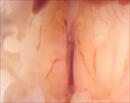

Caption: Mutant 1879-006-NC shows kidney agenesis (details)

b2b1879.2Clo, Mutant line 1879.2; Bench to Bassinet Program (B2B/CVDC), mutation 1879.2 Cecilia Lo

b2b1879Clo, Mutant line 1879; Bench to Bassinet Program (B2B/CVDC), mutation 1879 Cecilia Lo

Copyright: This image is from the Laboratory of Dr. Cecilia Lo, a member of the Cardiovascular Development Consortium (CvDC), Bench to Bassinet (B2B) program of the National Heart Lung and Blood Institute (NHLBI), and is displayed with the permission of the authors. J:175213